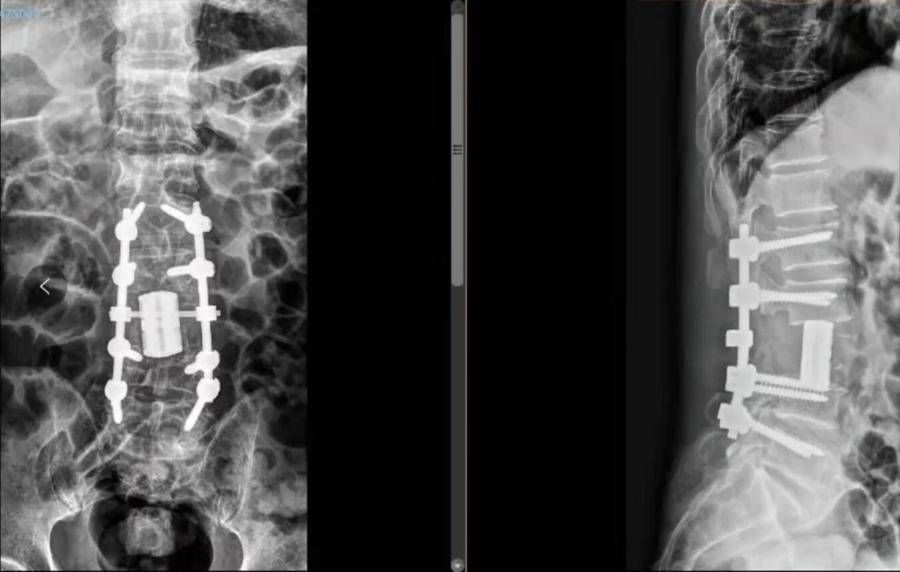

术前3D打印规划术中人工椎体大小形态。

【 椎体|烟台山医院成功完成全脊柱肿瘤切除+3D打印人工椎体置换术】“该患者手术的难点,一是出血多,椎体转移瘤患者术中出血比较多,需要术前做对肿瘤节段动脉栓塞来减少术中出血;二是风险大,单纯后路手术从后方把肿瘤切除,需要保护椎体前的大血管和椎体后的脊髓;三是剥离难,腰椎椎体全切,该部位侧前方有强大的腰部肌群等软组织附着,剥离困难,前方有主动脉等重要血管脏器,要在手术过程中仔细保护;四是创伤大,围手术期管理困难,需要多学科团队协作完成;五是重建难,腰椎活动度大,重建稳定性要求更高,使用传统的钛网置入跨度太长,远期会出现松动、塌陷等并发症,椎体形态不规则,椎体接触面角度变化大,因此使用了3D打印个体化制定人工椎体来解决脊柱稳定问题。”杜伟解释说。